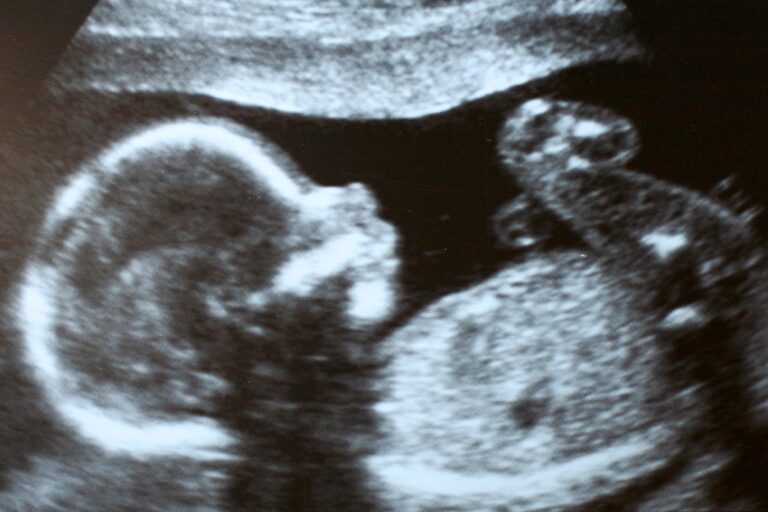

- Ultrasounds performed: 1,118

Recently, a young woman came into Birth Choice seriously considering abortion. This is what she said on her exit interview: “[Birth Choice] showed me a different view. They helped me with my decisions. [Seeing the baby on ultrasound was my favorite part] because I always wanted a family. Everything was great. They are gentle and understand your needs.”

“Angela” (pseudonym) was only five weeks and six days along, but the ultrasound nurse at Birth Choice detected a heart rate that was well over 100 beats per minute. It was seeing that heartbeat and recognizing her child’s humanity that changed Angela’s mind on having an abortion. That day, she chose to give her baby life! Fun fact: the earliest heartbeat the Birth Choice staff have seen on their ultrasound machines is at five weeks and five days. Ultrasound is truly a gift from God!

When “Jenna” (pseudonym) first stepped through our doors, she carried a heavy heart, feeling emotional, embarrassed, and disappointed in herself. She hadn’t been to church in the last year, and in that timeframe, she had been in a relationship with a verbally abusive man. So when she found herself pregnant for the first time, she thought abortion was the best option. However, our dedicated advocate enveloped her in warmth and understanding, reminding Jenna that she is deeply loved and cherished, not only by us but by Jesus. As Jenna soaked in the heartfelt information about parenting resources, adoption, and the realities of abortion, she felt empowered to explore the life-affirming options before her. Given her history with depression and suicidal thoughts, she especially resonated with the insights on post-abortion trauma. After talking with her advocate and seeing her baby’s heartbeat on ultrasound, Jenna realized that choosing life is the best option for herself and her baby! She also said she might consider going back to church, and she scheduled an orientation for our ESTHER parenting and childbirth program. Please pray that God will protect and provide for Jenna and draw her to Himself!

- “Krista” came to our bus in Brownsville when she was carrying her first baby, so she knew who to turn to when she got pregnant again in 2024. She considered abortion when she first boarded our bus, but after talking with our advocate about all her pregnancy options and resources available to her, she said it “cleared her mind” and she chose life! This is why accurate information is so powerful, and Krista’s advocate made sure to go over everything in detail. During her ultrasound, Krista saw the heartbeat of her seven-week baby.

- “Serenity” had seen our Mobile Clinic parked in the old Fred’s parking lot in Bolivar, so after testing positive with a home pregnancy test in 2024, she gave us a call. When she boarded our bus, she was torn between abortion and parenting. Her Volunteer Advocate shared what happened next: “during the ultrasound, her baby absolutely ‘showed out’ with the most clearly defined image we’ve seen at eight weeks. In addition, the baby’s heartbeat was strong, loud, and audible. It would appear…this baby wants to live! Following the ultrasound, both [the nurse] and myself asked (separately) that based on what she saw and heard – what decision – if any – has [Serenity] made. She actually – for the first time – gave a smile and said she was going to keep her baby.” Praise God for prompting this baby to be active and touch his/her mother’s heart